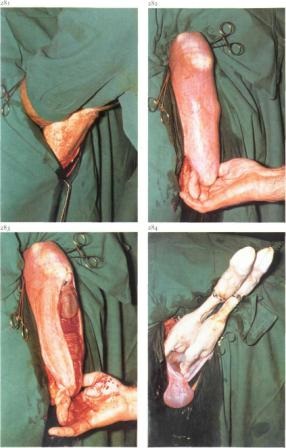

Vaci cezariene în trecut a fost folosit numai în cazuri foarte rare. Astăzi, datorită unei metode bine dezvoltat, care operarea cu un rezultat pozitiv, se realizează nu numai în spitale, dar, de asemenea, în mod direct într-un pro-ducerea. Vacile pot fi operate într-o poziție verticală (un animal da naștere la mașină, strângeți coarda la gard). Și numai slăbit animalele, incapabil să stea, să opereze într-o poziție culcat pe spate. Pregătiți locul intervenției chirurgicale.

Anestezie locală: paralyum punct anestezierea I. I. magde, la care a blocat ultima intercostal (n intercostalis.), Iliohipogastric Și ilioinghinal (n ilioinguinalis.) Nervi, sau o anestezie prin infiltratie (n iliohypogastricus.). Aplicați abordările chirurgicale superioare, de mijloc și de jos din stânga. Vacile cele mai des utilizate oblic medie și secțiuni verticale, cât și din accesele inferioare - ventral-lateral. secțiune verticală începe de la partea de jos fovea de colț foame și trece parakostalno. incizie Oblique, padding pe palma makloka în direcția comună carpian. incizie ventro-laterală - de la genunchi ori peste baza ugerului, în direcția arcului de margine craniană (la o distanță de 10-12 cm deasupra venei abdominal subcutanat). Lungimea tuturor tăieturile de la vaci de 25-40 cm (Fig. 114).

Fig. 114. Cele mai frecvent utilizate abordari chirurgicale pentru cezariana secțiune transversală a vaca:

/ - medie verticală; 2- 4- oblica mediu; 5 - ventrolateral

Atunci când accesul mediu la nivelul uterului este disecat pielii secvențial (simultan) cu țesutul subcutanat, fascia superficială, mușchiul subcutanat, fascia galben, extern și intern mușchiul oblic și aponevroza mușchiului transversal. Mușchii sunt tăiate în straturi fără a ține cont de direcția de deplasare a fibrelor musculare. Tăierea fascia transversal cu fibre retroperitone cial, pensete și ridicați ușor peritoneul tăiat prin ea, astfel încât cavitatea abdominală include indexul și degetul mijlociu de la mâna stângă. Sub controlul degetelor de incizie peritoneale se extind foarfecele drept în lungimea plăgii. După deschiderea peritoneului și cicatrice omentul cât mai mult posibil, este deplasată în cadranul superior stâng. Introdus în direcția craniană detectată mână-plodovmestilischa vârful corn, se strânge la rană și scos vârful corn. Fixarea mâna stângă când cefalică prezentare membrele din spate, în timp ce pelviana - șef al fătului, uterul este disecat, astfel încât cavitatea sa mers obstetrician mâna. După ce ați așteptat până când apa se va abate mâna dreaptă la nivelul membrelor din spate sau din față fixă a fătului și scoateți-l spre exterior. Apoi, incizie uterin (ocolind placenta) Uwe-lichivayut la lungimea dorită și după membranele disectia recuperate lent fetus. La extracție excesiv de rapidă a vidului fetal este creat în cavitatea abdominală, ceea ce duce la o scădere bruscă a tensiunii arteriale. Cordonul ombilical a fost terminată și transferat la fat sa se descurce ca o naștere normală. În cazul în care ultimul este separat liber, atunci acesta este scos din uter. De obicei, acest lucru se întâmplă în prezența fetuși morți. Atunci când se ocupă cu o vacă Secv fat viu separate cu dificultate apare sângerare abundentă. Prin urmare, acestea sunt lăsate în uter. Pentru a grăbi biroul său, după sutura miometrul uterului injectat 4-5 ml pituitrina sau 40-60 unități de oxitocină și să dea o vacă linge un vițel cu grijă.